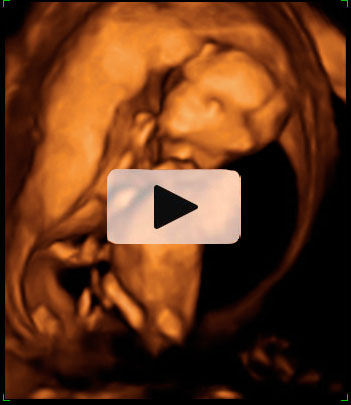

Ecografía Embarazo 4D - SEMANA 12